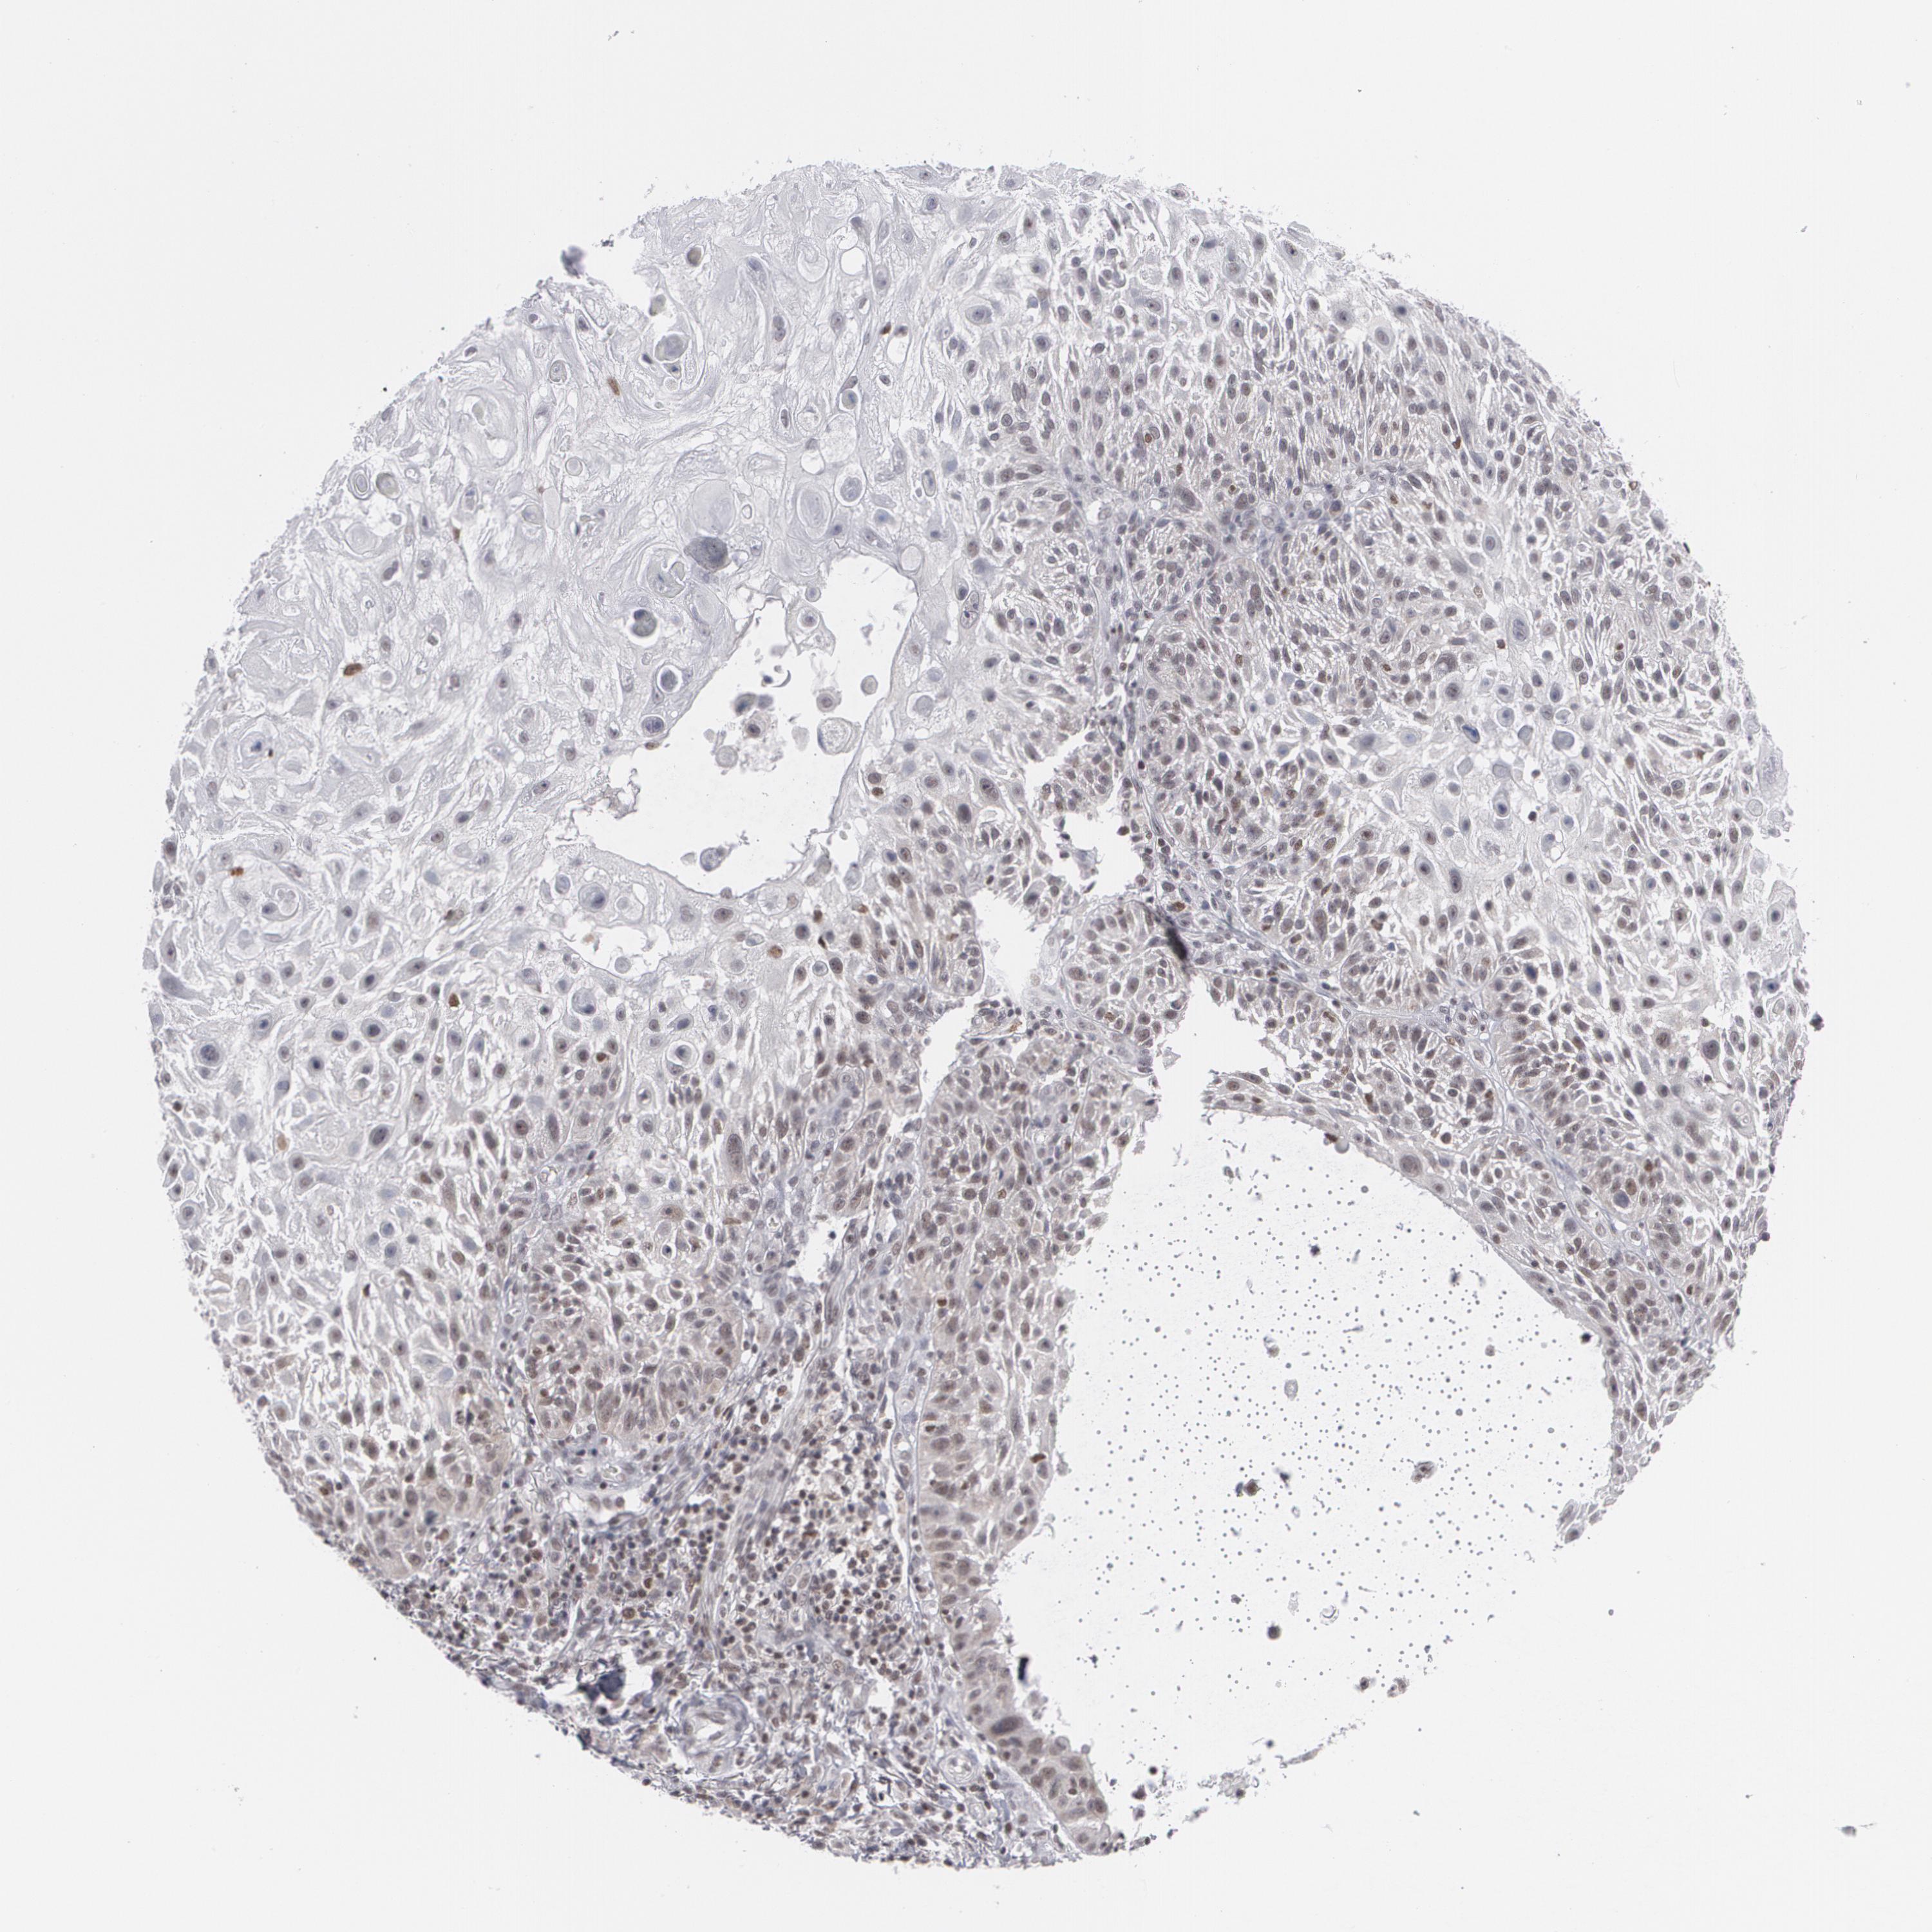

SKIN CANCER - Protein expressioni

A mouse-over function shows sample information and annotation data. Click on an image to view it in a full screen mode. Samples can be filtered based on level of antibody staining by selecting one or several of the following categories: high, medium, low and not detected. The assay and annotation is described here.

Antibody stainingi

Antibody staining in the annotated cell types in the current human tissue is reported as not detected, low, medium, or high, based on conventional immunohistochemistry profiling in selected tissues. This score is based on the combination of the staining intensity and fraction of stained cells.

Each image is clickable and will lead to virtual microscopy that enables deeper exploration of all samples and also displays staining intensity scores, fraction scores and subcellular localization as well as patient and tissue information for each sample.

Antibody HPA008455

Antibody HPA031125

Antibody CAB002781

Antibody CAB068195

Squamous cell carcinoma, NOS

Squamous cell carcinoma, metastatic, NOS

Basal cell carcinoma

Papilloma, NOS